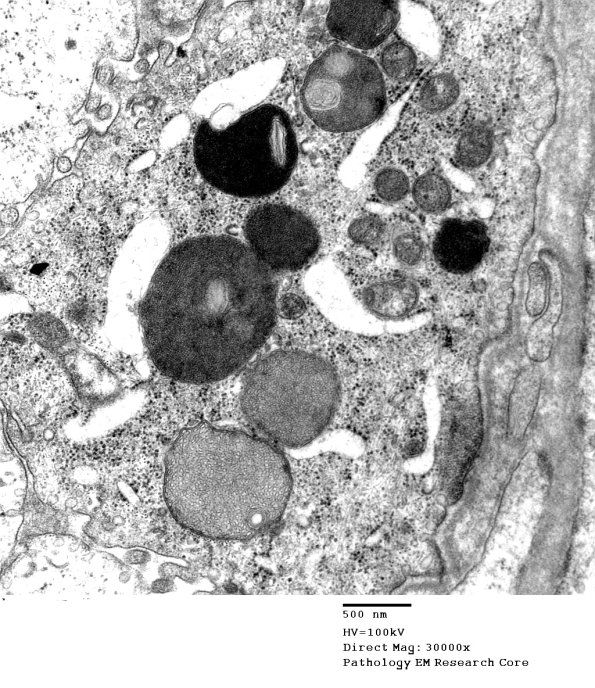

2B5,6 Higher magnification of the osmiophilic inclusions. (electron micrographs)